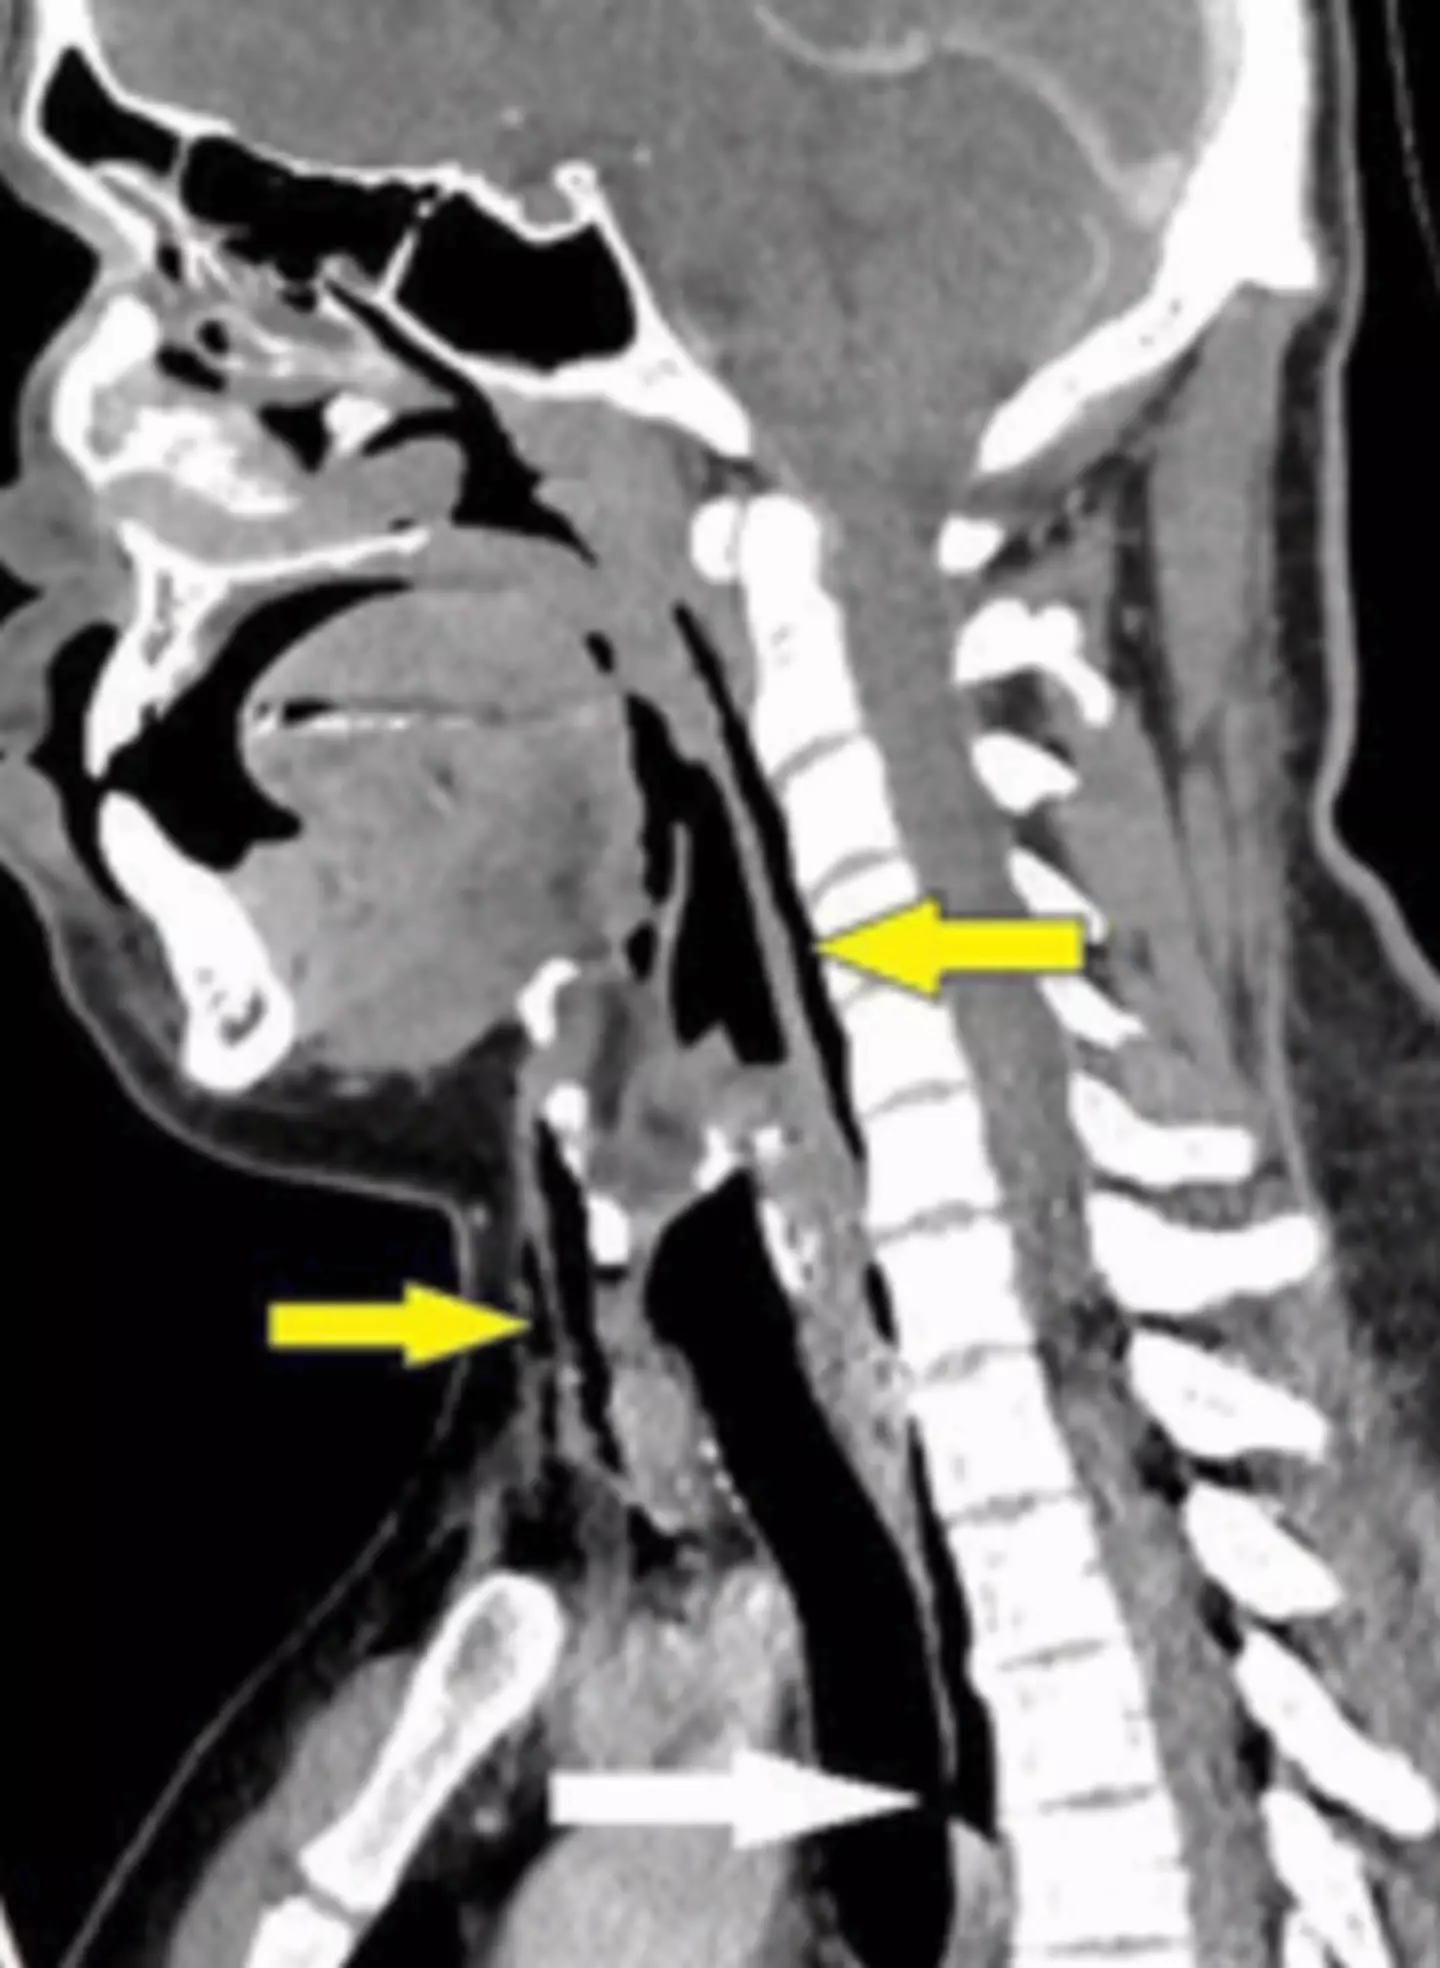

The patient then underwent an X-ray and CT scan, which revealed he had a 2 mm × 2 mm × 5 mm tear in his trachea - known as a 'tracheal perforation'.

The patient was also found to be suffering from surgical emphysema which 'occurs when air or gas enters the subcutaneous tissue, which is the deepest layer of the skin,' as per Medical News Today.